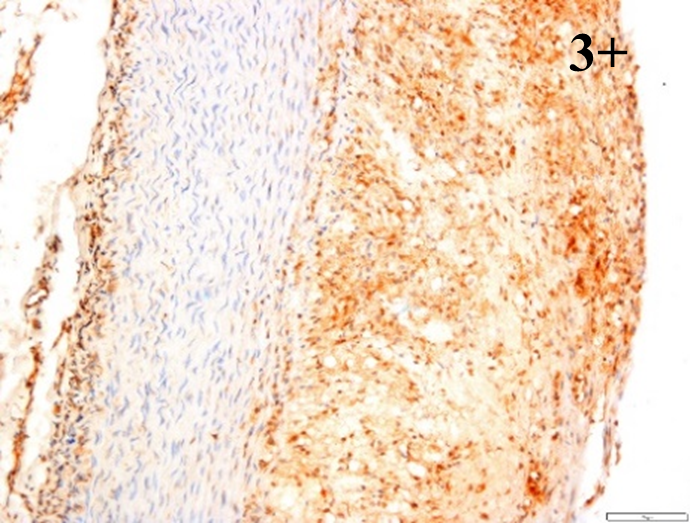

Immunoreactions of ICAM-1, VCAM-1, e-selectin, IL-6, IL-8, NF-

According to the percentage endothelial staining of cells, semi-quantitative

scores were applied. Score: 0 (negative); 1+ (1–10% positive cells); 2+

(11–25% positive cells) and 3+ (

Medium to high expressions of adhesion molecules, such as ICAM-1, VCAM-1 and

e-selectin were observed in the aortas of rabbits fed with HCD. This represents

the initiation of the lesion stage, where the endothelial cells have been

stimulated by the ox-LDL to express the adhesion molecules, which could lead to

the recruitment of monocytes and transmigrate into the intima by diapedesis as

well as differentiate into pro-atherogenic macrophages [47]. An increased

expression of pro-inflammatory biomarkers, such as IL-6, IL-8 and NF-